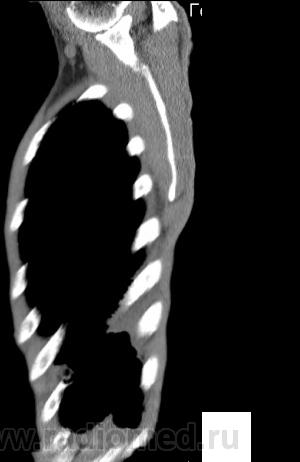

На фоне консолидации полость без содержимого. Может быть всё что угодно, что сопровождается деструкцией. Нужны ещё томограммы в лёгочном окне.

Изображения выставлены все. Ваше мнение уважаемые коллеги?

Это КТ 2-летней давности и попало оно мне в руки, после недавнего прохождения контроля пациентом, когда мы стали перед вопросом о специфическом / не специфическом процессе.

Тогда, пациента 2 месяца лечили от пневмонии, лечили интенсивности, стационарно, в серьёзном учреждении.

Предположу аспергиллез